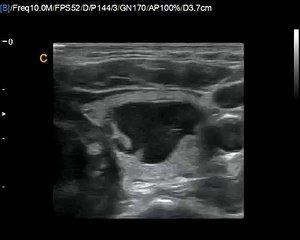

Neck Examination(thyroid, cyctic nodule, thyroglossal cyct)

The patient should hold a glass of water and be seated. There should be room for the examiner on all sides of the seated patient. Place the patient's head in slight hyperextension with good crosslight falling on the anterior neck and then ask the patient to swallow. The outline of the thyroid gland in thin individuals can be observed frequently as a protuberance on both sides of the trachea moving cephalad in tandem with but 2 cm below the crest of the thyroid cartilage (Figure 138.1). Look for abnormal enlargement, contour, asymmetry, and masses while the patient swallows repeatedly. The neck should also be inspected for abnormal masses and prominent pulsations. br br The art of thyroid gland palpation has spawned a number of distinct attitudes, and each examiner should, through practice, adopt a comfortable technique. Frequently it is advantageous to examine the gland while you stand behind as well as on each side of the patient. Identify the thyroid cartilage, the thyrocricoid membrane, and the cricoid cartilage, a horizontal structure 5 mm wide that marks the superior border of the isthmus. Palpate the isthmus (frequently impalpable unless enlarged), and if standing to the side of the patient, slide the tips of your fingers so that their palmar surfaces rest on the trachea with the dorsal surface medial to the sternocleidomastoid muscle. A frequent mistake is to move the fingers too laterally and trap the body of the muscle between your fingers and the trachea. The ipsilateral lobe can be palpated simultaneously with your thumb or with the other hand from the opposite direction. When you stand behind the patient, identify the landmarks and isthmus with one hand, and when in position to feel the thyroid lobe on that side, place the fingers of your other hand symmetrically on the other side of the trachea. Again identify each lobe while the patient swallows. Feel the gland's surface, note any asymmetry, texture, and estimate the size of each lobe (normally 7 to 10 g). When goiter is present, measure any discrete masses as well as the neck's greatest circumference. A penciled tracing of the goiter's outline provides a reliable record for future comparison. One should also palpate the neck for lymphadenopathy and search for masses (especially in the midline for abnormalities of the thyroglossal duct) and surgical scars. br br Transillumination is helpful only in confirming the nature of a superficial thin-walled cyst. Occasional patients with Graves" disease present with an auscultable bruit and palpable thrill over a diffusely enlarged goiter.